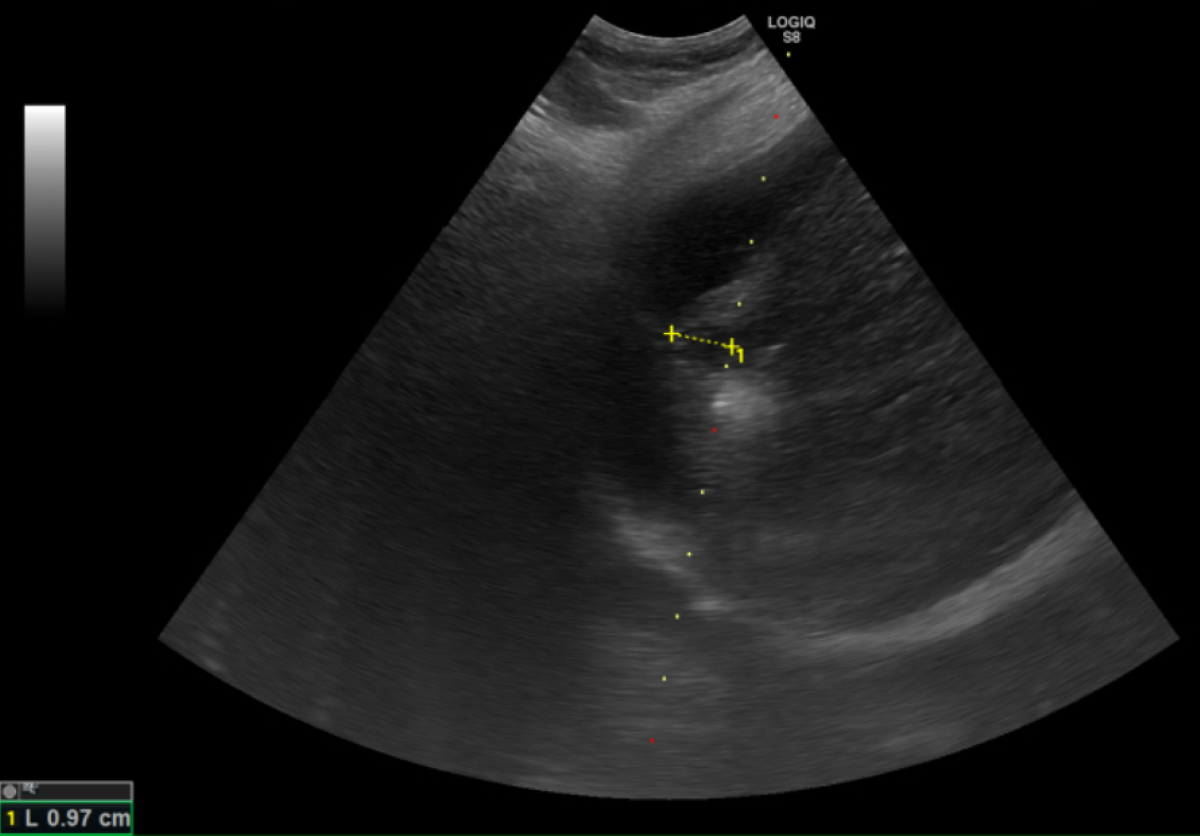

根據臨床數據,零期肝癌治療後平均存活率超過10年以上,若延誤至第二期則縮短為約5年,第三期降至2.5年,若已轉移,存活時間僅剩半年。「在第零期使用電燒治療普遍可根治,不需要化療,已經有遠處轉移才會考慮使用免疫療法及標靶治療。」鄭煜明醫師解釋,電燒治療是透過超音波導引定位,使用電極產生電流,造成離子震動產生超過60度的熱能氣化腫瘤,比起手術能更完整保留健康的肝臟組織。鄭煜明醫師進一步說明,肝癌患者平均5年的復發率高達七成,因此電燒治療對於可能復發,需要多次治療的患者而言更具優勢,且此療法住院時間短,通常三日左右即可出院。適應症方面,電燒治療適用於單顆或三顆以下、每顆腫瘤不超過三公分的個案,且腫瘤位置不能靠近心臟、肺臟等重要器官。治療前需評估凝血功能,若有凝血嚴重異常且無法透過治療矯正者,則不適用電燒治療。